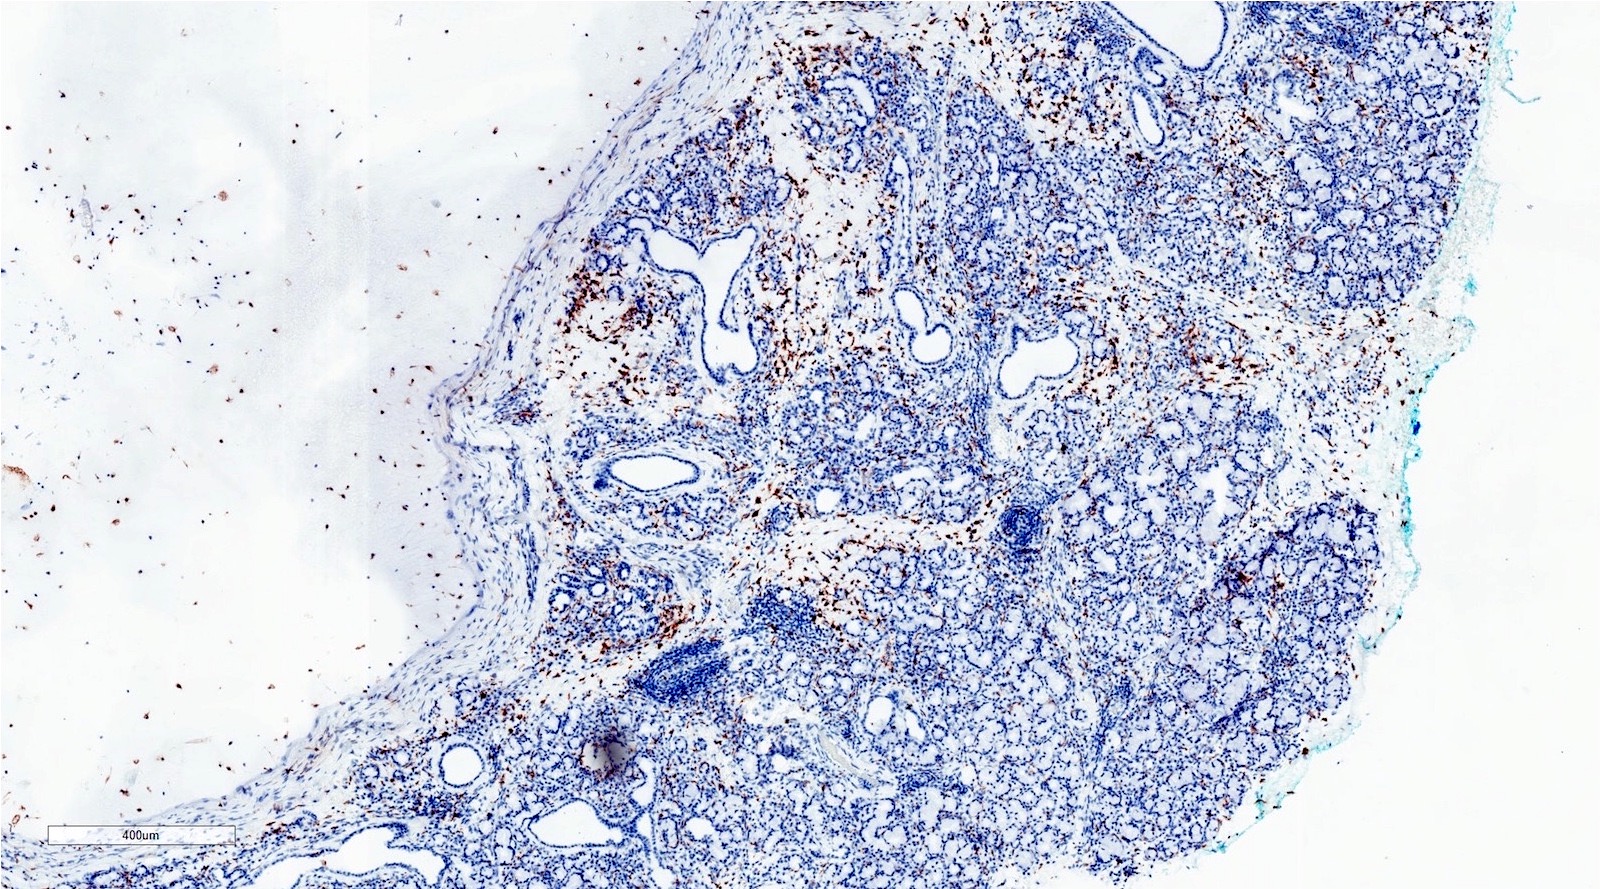

Microscopic (histologic) images

Positive stains

- Note: stains typically not needed to make the diagnosis

- CD68

- PAS-D

- Mucicarmine

- Alcian blue